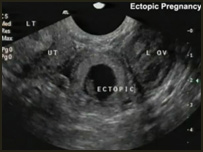

دوکتوران، اکسريز را برای خانم های حامله کار خطرناک دانسته و مناسب ترين معاينه را برای آنان ، التراسوند يا به گفته مردم معاينات تلويزيونی می دانند.

تا حد امکان کوشش شود که نزد خانم های حامله از التراسوند يا به اصطلاح مردم معاينه تلويزيونی استفاده شود.

چرا که اين معاينه مشکلات موجود در نقاط مختلف بدن، مانند:

جگر، پانقراص، کيسه صفرا ،معده، گرده ها ، مثانه و روده ها، رحم يا بچه دان، تخمدانها و جاهای ديگر بدن را نشان داده می تواند.

داکتر ملالی جاويد، متخصص التراسوند می گويد : معاينات تلويزيونی به واسطه سوند يا صدا اجرا می شود واز هيچ گونه شعاعی جهت اجرای اين معاينات استفاده نمی شود.

بنابرين به طفل ويا مادر، هيچ نقصانی متوجه نمی شود، بلکه اجرای آن در زمان حمل به خاطر دانستن وضيعت طفل در داخل رحم مادر بسيار ضروری هم است.